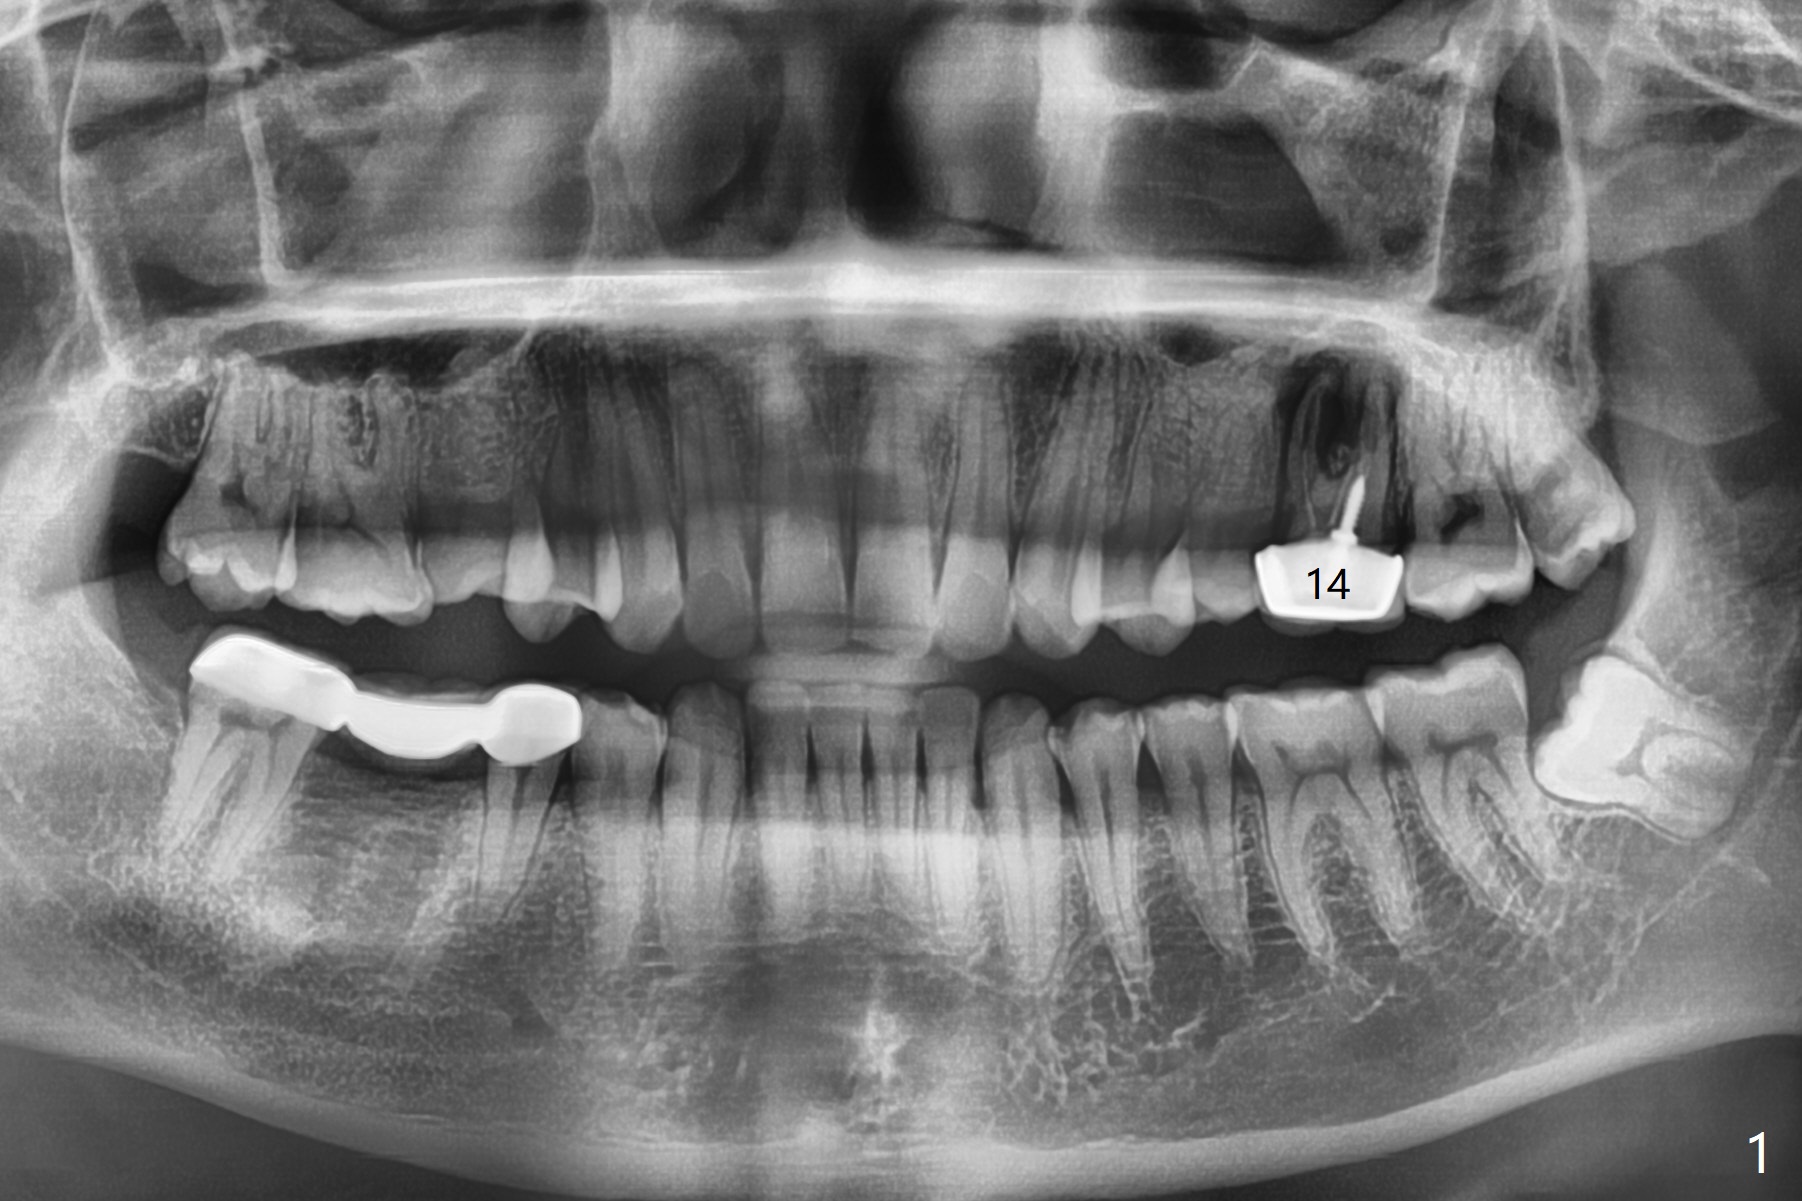

A 29-year-old man has pain in the upper left quadrant. It appears that the tooth #14 has endo and post failure with palatal fistula (Fig.1,2). The septum is almost non-existent; the palatal wall is low, while the sinus floor is present. Sticky bone is placed first against the defective palatal wall and presumably pushed as high as to the sinus floor (Fig.3-5). PRF plug/membrane and 6-month membrane are used to close the socket with 4-0 Chromic gut suture apparently securely, followed by periodontal dressing. Examination of the extracted tooth shows granulation tissue between the roots (Fig.6 *). Underneath the granulation tissue is cement-like material (Fig.7 C). Distal-to-mesial X-ray examination shows possible furcation perforation (Fig.8 *), while mesial-to-distal one the cement-like material in the furca and pulpal chamber as well as MB2 (Fig.9 >). The patient returns 8 days postop, reporting pain reduction, but wants to have #16 extracted. The periodontal dressing is loose, but stuck with 2 sutures underneath. When the dressing is removed, the wound looks normal (Fig.10). In fact the dressing is re-applied. The 6-month membrane has lost 1 month postop. The majority of the socket heals except the palatal (Fig.11 *), as related to the existing palatal fistula/defect (^). Orthodontics is being considered. If the buccal plate collapses 4.5 months post extraction, socket shield should have been done. In fact the buccal plate is robotic, while the bone density is low palatal in CT (Fig.12).